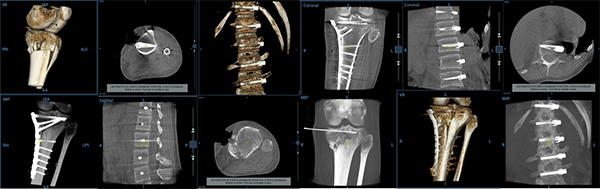

OEC 3D は,術中の3Dおよび2D撮影に対応したモバイルCアームです。OEC Elite CFDシリーズ搭載の2D撮影向け機能を踏襲しつつ,高精度・高効率な術中3Dイメージングを可能にする様々な機能を搭載しています。

3Dスキャン時に19cm×19cm×19cmの広い視野サイズで一度に多くの対象を撮影することが可能です。一辺16cmで撮影した場合と比較して,167%の広い領域を一度にカバー可能であり,スムーズな手術進行を支援します。

3D撮影時はプロジェクション数を200または400から選択でき,更に高線量モード/低線量モードと組み合わせて最適な撮影条件をフレキシブルに選択可能です。患者様ごとに最適化された5123 Voxelの高解像画像を提供します。

3D撮影中心を変えないIsocentric撮影方式を採用し,正確なスキャンを実現。撮影時間30秒で200°回転,かつ撮影中に線量を可変させることにより3D画像の高画質化と患者様の負担軽減を両立します。